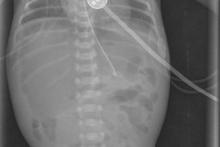

Noworodek w 7-ej dobie życia z podejrzeniem perforacji przewodu pokarmowego.

Przypadek 9: Noworodek w 7-ej dobie życia (wcześniak urodzony w 26 Hbd) z podejrzeniem perforacji przewodu pokarmowego.

Rozpoznanie: Na zdjęciach przeglądowych klatki piersiowej i jamy brzusznej (a-p w pozycji leżącej i boczne poziomym promieniem) uwidoczniono wolny gaz (strzałka) pod przednią ścianą jamy brzusznej - perforacja przewodu pokarmowego.

Pytanie: Jakie są cechy perforacji przewodu pokarmowego na zdjęciach rtg? Czy można rozpoznać obecność wolnego powietrza w jamie brzusznej na zdjęciu a-p wykonanym w pozycji leżącej (np u małych dzieci lub pacjentów w OIOM) ?